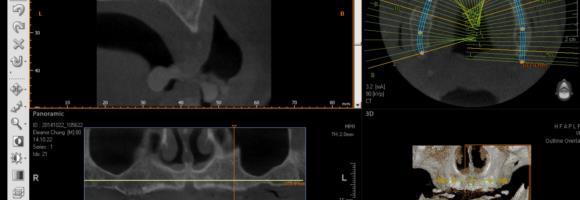

Compare a CBCT taken in 2011 vs in 2015, is there a difference? When is a good time to get a scan? A CBCT Scan is no longer a priviledge but it is a must diagnostic tool in Implant Dentistry. It gives you 3 dimesional view of a site, allows you to estimate proximity of vital structures such as a nerve or a sinus, you can study the anatomy, you can virtually plan a case, with or without a surgical guide.

Saying that scan is not necessary will soon be like stating xray is not essential. New CBCT machines deliver low dosage, fast scans for every clinical need..